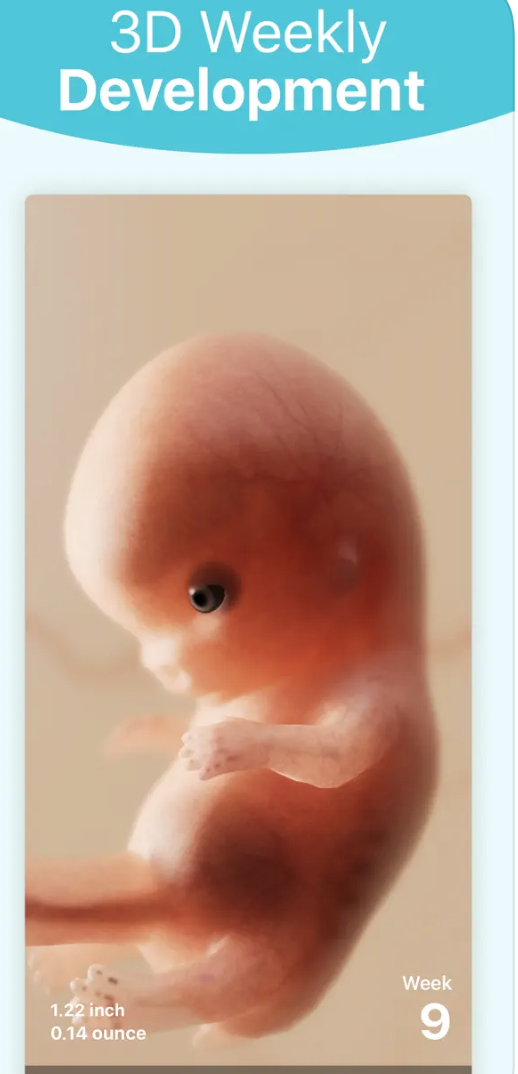

Jak název napovídá, aplikace Pregnancy+ je určená těm, kterým se již podařilo počít potomka. Pregnancy+ vás provede vaším těhotenstvím od začátku až do konce, bude vám neustále podávat související informace, zajímavosti a tipy. Najdete zde užitečné články, zajímavé ilustrace a 3D modely a spoustu dalšího.